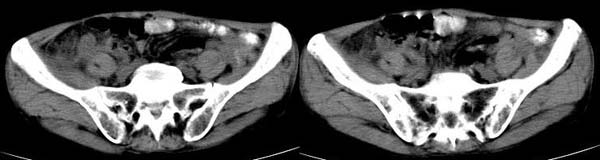

男 74岁,聋哑人,病史不详。

右半结肠不规则 弥漫性增厚,与周边胀器分界清楚,建议行钡剂灌肠.单纯本片还是考虑:升结肠癌.

升结肠壁不均匀增厚,肠腔偏心性狭窄,周围境界尚清,腹主动脉旁、盆腔内未见肿大淋巴结,考虑:升结肠癌可能性大.建议:纤维结肠镜检查.

1.结肠癌,2.回盲部炎变  [盲升结肠壁不均匀增厚,盲肠边缘模糊]